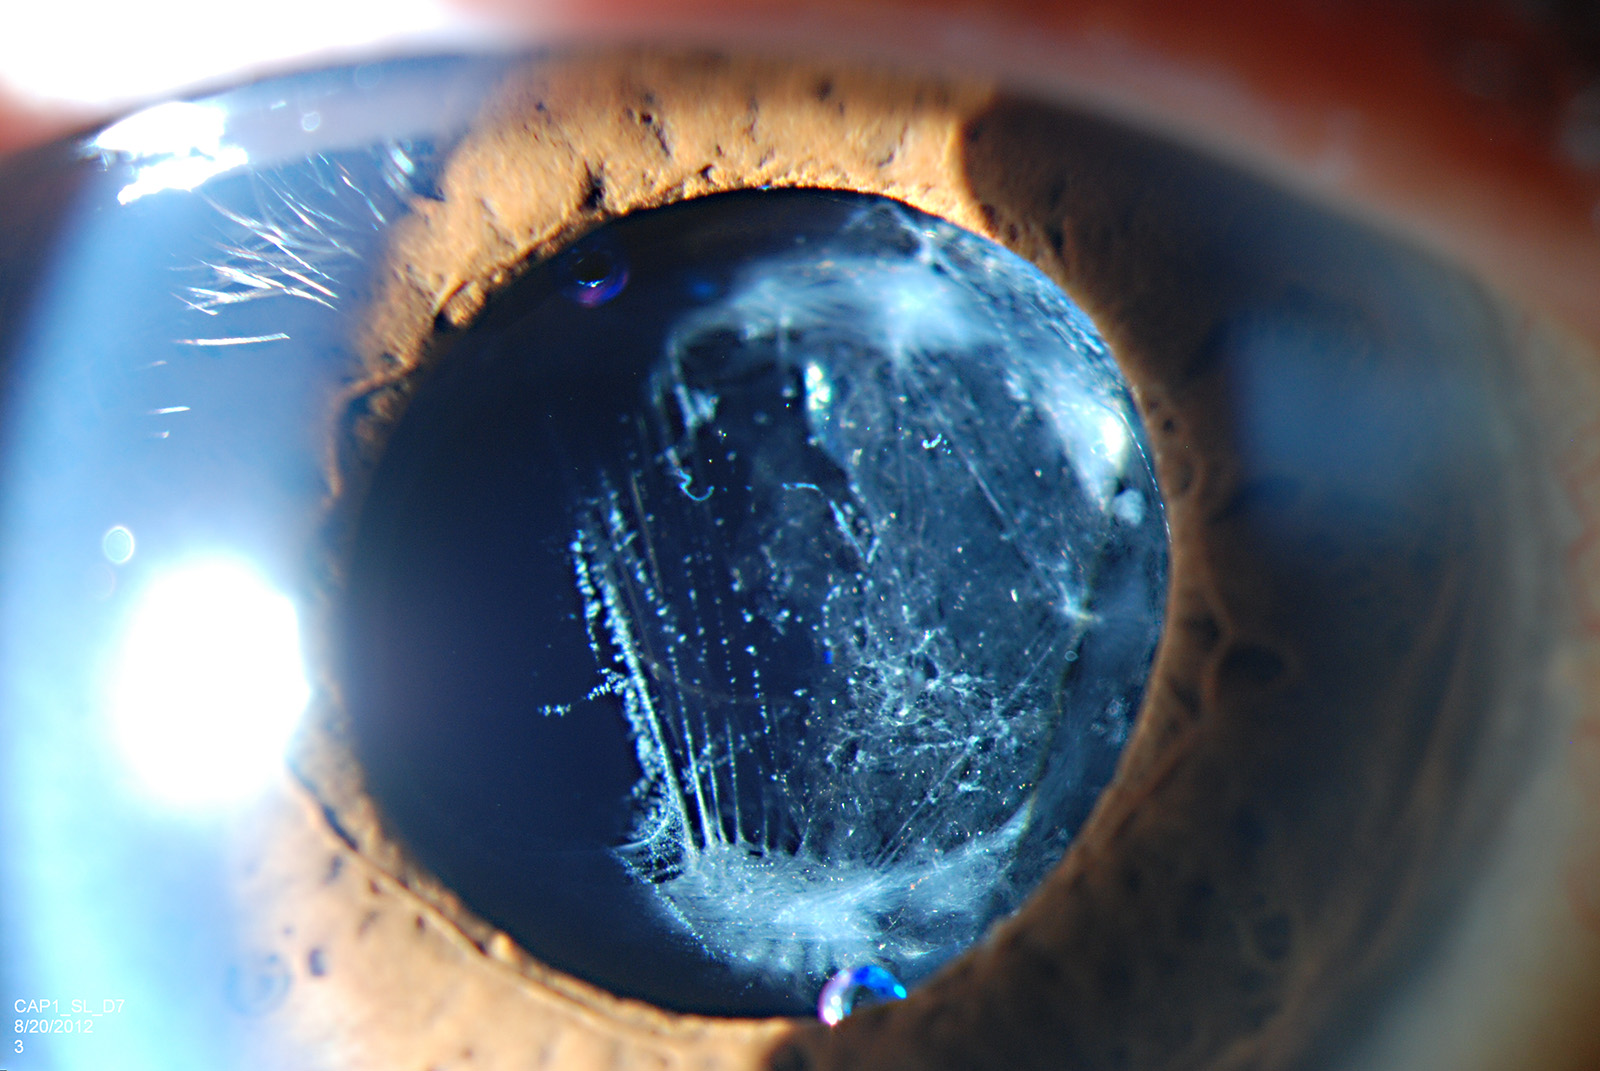

Posterior capsular opacification Download Scientific Diagram

Posterior capsular opacification (PCO) scoring by slit lamp derived Posterior Capsular Opacification Visually Significant posterior capsular opacification (secondary cataract) is a clouding of the thin membrane (lens. posterior capsular opacification (pco), also known as “secondary cataract”, is a common. to analyse the posterior capsular opacification (pco) development pattern in the long term in eyes implanted. posterior subcapsular opacification can cause significant visual impairment after cataract surgery. Posterior Capsular Opacification Visually Significant.